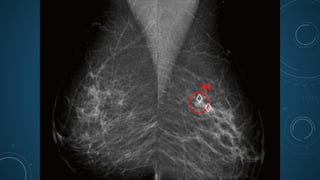

• These solutions become smarter and more adept at identifying cancer as

they are trained on breast imaging data, automatically highlighting

suspicious areas and enabling radiologists to focus on areas they should

review more closely.